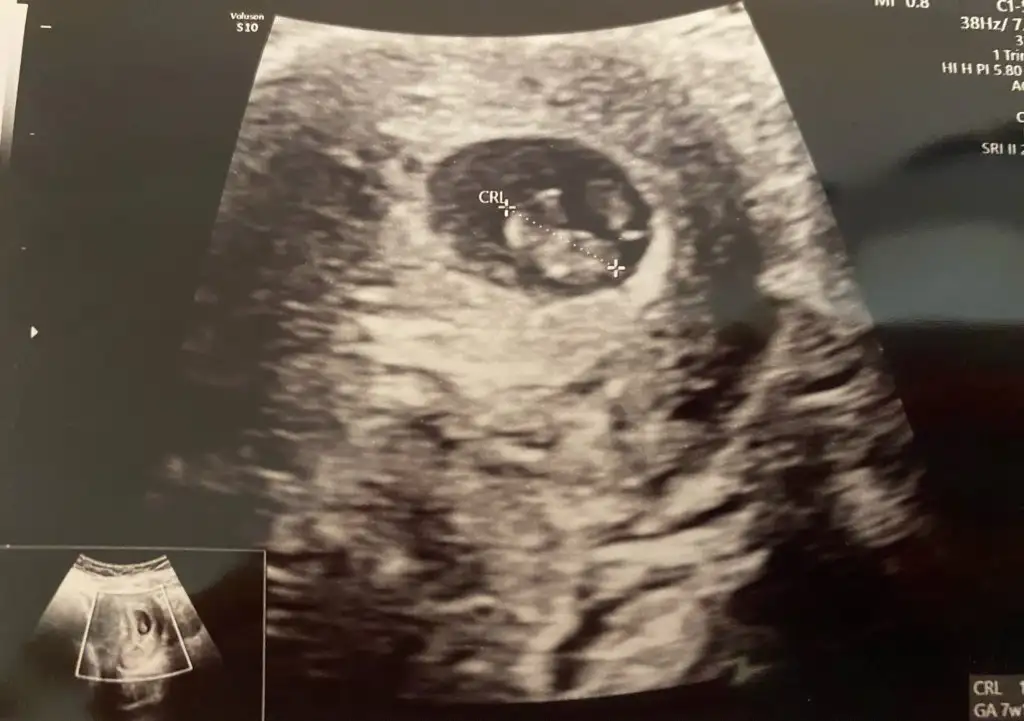

Merhabalar bizimde bebeğimiz 12 haftalarda yorumlarsanız çok sevinirim Ikra meyra Ikra meyra